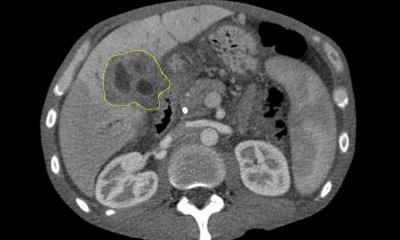

Erste Therapieerfolge waren schnell zu erkennen: Das Wasser in der Lunge ging zurück, sodass sich die Atmung verbesserte. Der Tumor schrumpfte von etwa faustgroß auf die Größe einer kleinen Mandarine. „Möglicherweise handelt es sich auch nur noch um Narbengewebe“, mutmaßt Jäger. Unter Nebenwirkungen litt Kessesidis kaum: „Etwas Durchfall hatte ich am Anfang und meine Schuppenflechte wurde schlimmer.“ Jäger ist stolz auf diesen Therapieerfolg, warnt aber gleichzeitig vor zu übertriebenen Erwartungen: „Nicht bei allen Patienten spricht die Behandlung so gut an. Bei manchen Betroffenen wirkt sie gar nicht.“